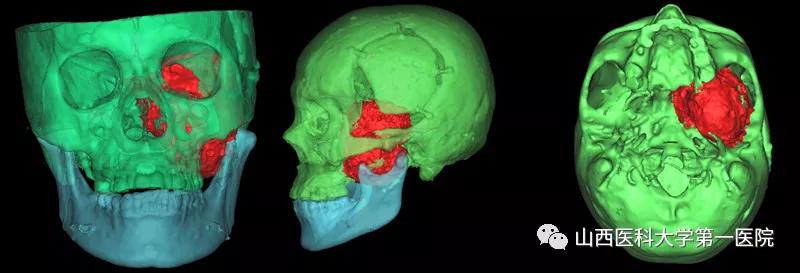

患者是一名老年女性,早在7年前诊断为颅底“胆脂瘤”,7年来已经接受了三次开颅手术治疗,近期出现的头痛、视力减退、面部麻木等症状预示着肿瘤可能再次复发。经MRI和CT检查后发现其肿瘤不仅复发,而且较以往体积明显增大,最大直径达8.5cm,最麻烦的是肿瘤所处的位置非常“尴尬”,像一颗“*弹炸**”深深地卡在了中颅底,约1/4部分瘤体位于颅腔,其余3/4凸向翼腭窝、颞下窝。“巨大的肿瘤体积、复杂的解剖位置、既往多次手术史”等不利因素,为本次手术治疗带来了巨大挑战。术前由医务处牵头组织由口腔颌面外科、神经外科、麻醉科、手术室等组成的多学科团队对手术方案进行了周密部署,对术中风险进行了充分评估并制定了应急预案。

经过对“手术入路、硬脑膜修补、颅底缺损重建、颈内动脉和海绵窦等毗邻结构保护”等系列高风险环节的反复研究,最终定为由口腔颌面外科先行颈-颌入路、上颌骨、颧骨部分切除,充分显露后先切除颅外3/4部分瘤体,再通过颅底骨缺损“窗口”由神经外科完成颅内部分瘤体的切除与硬脑膜的修补,最后采用股前外侧肌皮瓣游离移植修复颅底、翼腭窝、颞下窝巨大无效腔。为了使手术方案进一步可靠,口腔颌面外科团队术前采用数字化技术对手术入路进行了虚拟验证,并从三维立体方向对肿瘤周围的重要结构进行全方位掌握。